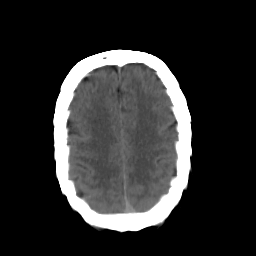

In this paper, we propose a bidirectional learning model, known as dual contrast cycleGAN (DC-cycleGAN), for medical image synthesis from unpaired data. Specifically, a dual contrast (DC) loss is formulated that leverages the advantage of samples from the source domain as negative samples to indirectly build constraints between real source and synthetic images via discriminators, and synthesize images more related to the target domain by enforcing the synthetic images to fall far away from the source domain. In addition, structural similarity index (SSIM) [35] and cross-entropy (CE) [48] are integrated into the DC-cycleGAN structure to avoid disappearing gradient information that is caused by a mean absolute error (MAE) and synthesizing irrelevant images. SSIM considers luminance [35] and CE converges fast as its back-propagation error is less than MSE [28]. As can be seen in Figs. 1 and 2, using SSIM and CE with dual contrast can generate more clear and accurate MR images as compared with that of MAE and MSE, and SSIM and CE without dual contrast loss. Although both SSIM and CE with dual contrast and without dual contrast generate similar CT images, SSIM and CE with dual contrast quantitatively generate better images as shown in Table 4. The experimental results indicate that DC-cycleGAN is able to consider more complex features such as structure in synthesizing images and produce remarkable results as compared with other state-of-the-art methods reported in the literature.

Tables 3 and 4 show the results of MR and CT synthesis, respectively. As can be seen, all components play vital role in both tables. SSIM & CE (w) performs significantly better than other losses in synthesizing MR images. This also can be seen visually in Fig. 1. In contrast, SSIM&CE (w) performs slightly better than SSIM&CE (wo) in synthesizing CT images, both generate more or less similar CT images (see Table 4).